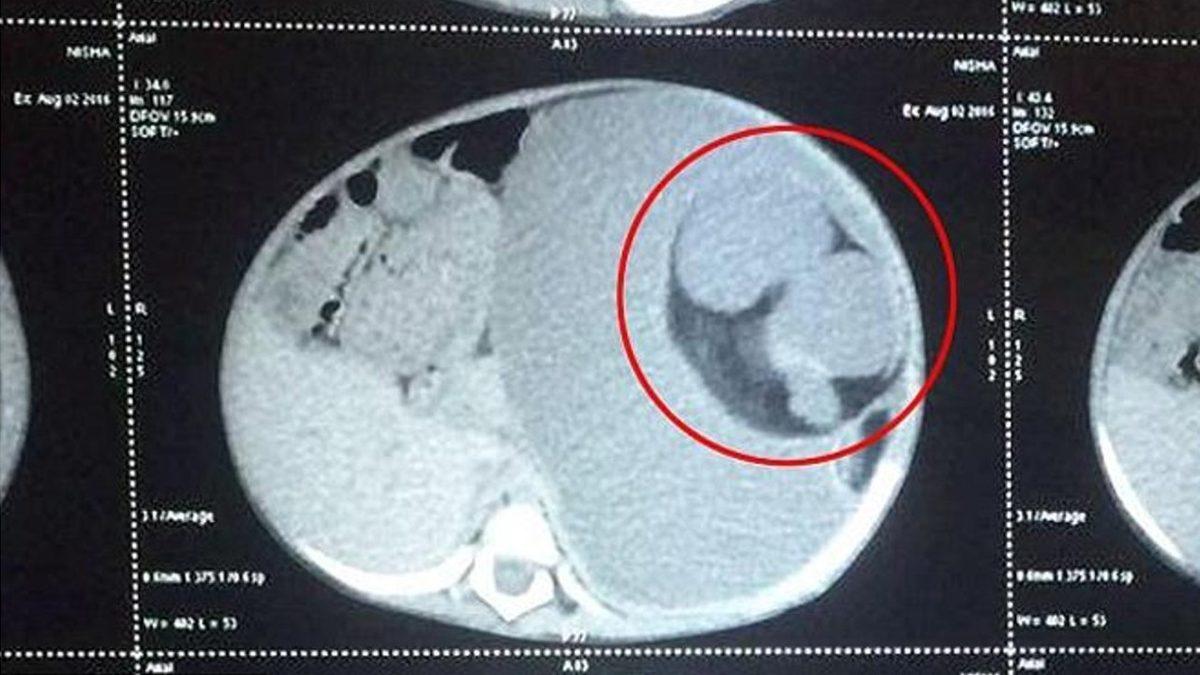

Bu sendromu gösteren fetüsün muayene esnasında karnı şiş, aynı zamanda yumuşaktı ve karnındaki kitleler belirgin bir şekilde ele geliyordu. Kitle fetüs görünümünde, uzuv benzeri yapılara, anormal iskelet ve bağırsak gelişime sahipti.

Olguların yaklaşık %80'inde bu anormal durum, normal fetüsün vücudunda karnın arka bölgesinde ortaya çıkıyor ancak göğüs, kasık ve kuyruk sokumu gibi vücudun diğer bölgelerinde de görülebiliyor.

Tanı ve tedavi için ise fetüs içinde yeni bir fetüs oluşumuna sebebiyet veren bu kitle, yeni doğan bebeklerin vücutlarına potansiyel olarak zarar verirken, ameliyatla çıkarılmalı ve incelenmelidir.